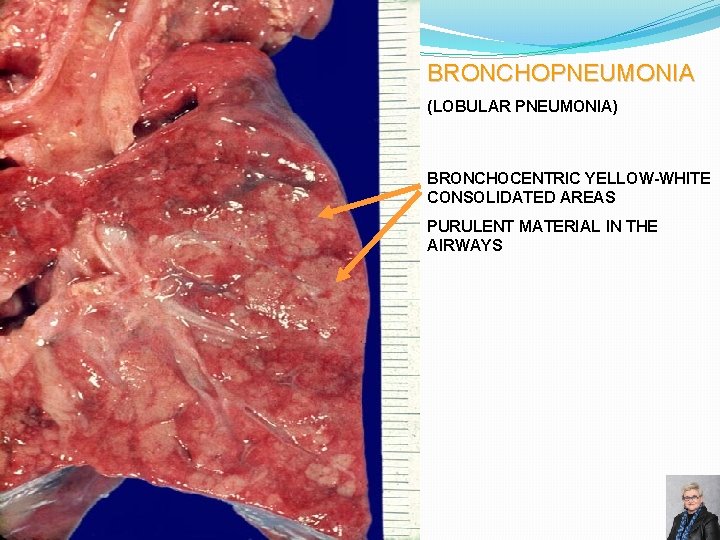

BRONCHOPNEUMONIA Gross morphology: � Scattered patchy consolidation centered around bronchioles – “lobular” pneumonia � Usually bilateral, multilobar and basilar Epidemiology: � Affects the young, old, and terminally ill Organisms: � Staphylococci, Streptococci, Haemophilus influenzae, � Pseudomonas aeruginosa and others Microscopic features: � Acute inflammation of bronchioles and the surrounding alveoli 67

BRONCHOPNEUMONIA (LOBULAR PNEUMONIA) BRONCHOCENTRIC YELLOW-WHITE CONSOLIDATED AREAS PURULENT MATERIAL IN THE AIRWAYS 69